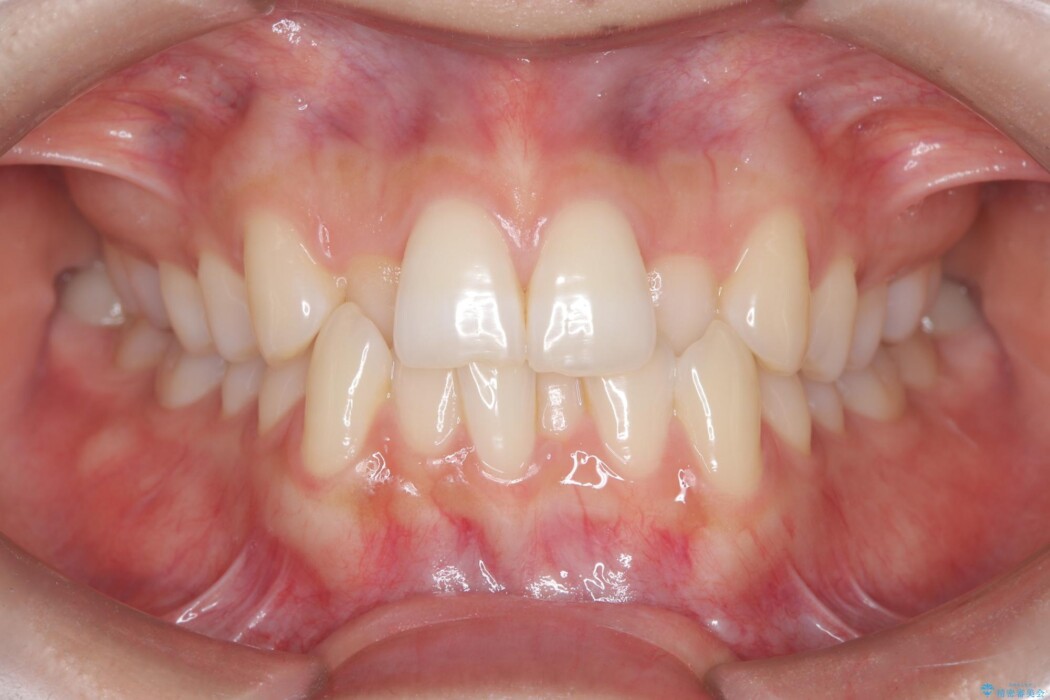

歯のガタつきが気になるとご来院された患者様です。

矯正検査の結果、非抜歯にてワイヤー矯正を行うこととしました。

ガタつきのほかに反対咬合も認められたため、見た目だけでなく嚙み合わせも同時に改善していきます。